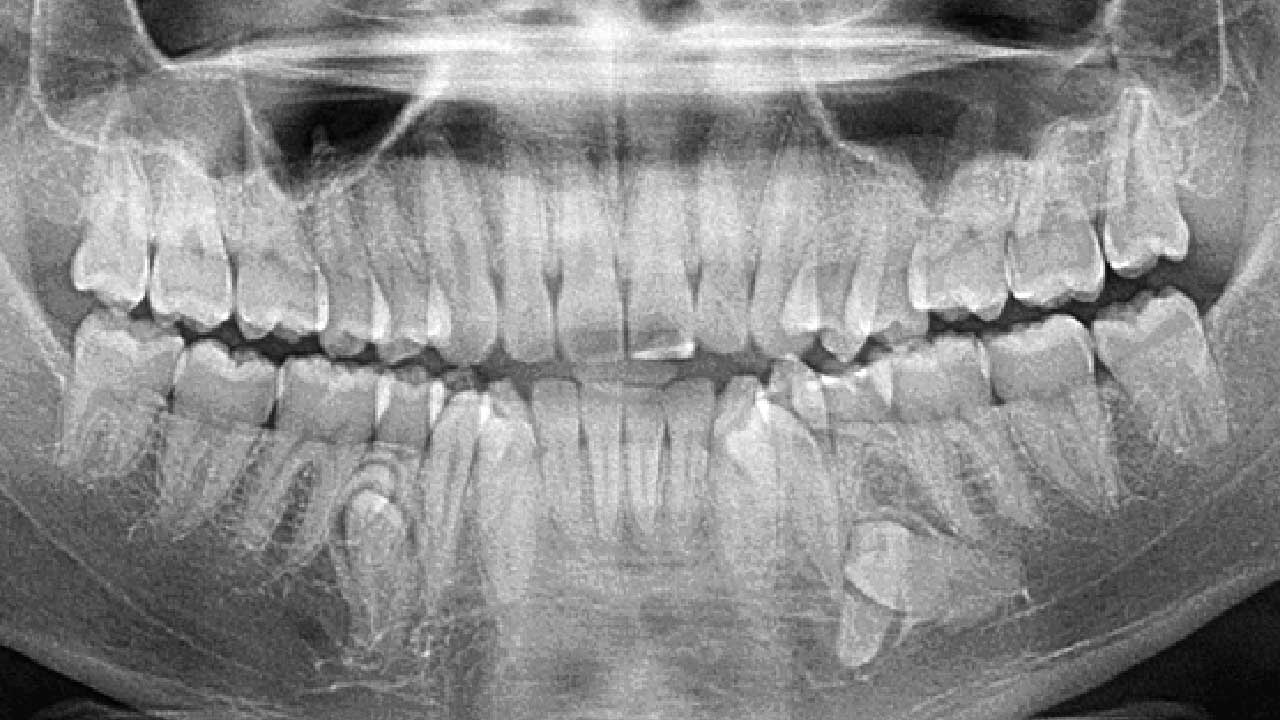

A unique world record has been set in India. A 26-year-old woman, Kalpana Balan, has a total of 38 teeth in her mouth—six more than the average person. Due to this rare condition, her name has been recorded in the Guinness World Records. This raises an important question: if someone has extra teeth, should they be removed or left as they are?

Typically, an adult has 32 teeth. However, Kalpana Balan has 4 extra teeth in the lower jaw and 2 in the upper jaw. These extra teeth began appearing gradually during her teenage years. While she does not experience significant pain, food often gets stuck between her teeth while eating.

This condition is known as Hyperdontia or supernumerary teeth, where more teeth develop than usual. It is observed in about 3–4% of the global population.

Overdevelopment of tooth buds

Genetic factors

Splitting of tooth buds into two